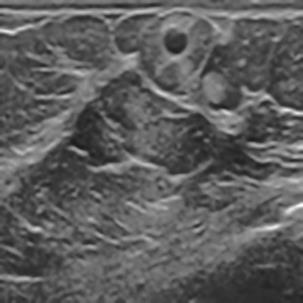

基于逐通道空间自适应选择核卷积与双向边界感知机制的乳腺超声图像病变分割网络

A Breast Ultrasound Images Lesion Segmentation Network Based on Channel-Wise Spatially Adaptive Selective Kernel Convolution and Bidirectional Boundary-Aware Mechanism

乳腺癌是全球女性最常见的恶性肿瘤之一,准确的病变分割对于乳腺癌的早期诊断与治疗具有重要意义。然而,由于病变形态的多样性以及超声成像机制的复杂性,现有基于深度学习的乳腺超声图像病变分割方法在分割准确性方面仍面临巨大挑战。为进一步提升乳腺超声图像中病变区域的分割精度,该文基于经典U-Net架构,提出了一种新型乳腺超声图像病变分割网络(CWSASKM-BBAM-Net)。首先,在网络中引入逐通道空间自适应选择核卷积模块(CWSASKM),根据不同通道的语义特征为每个空间位置自适应选择感受野大小,以增强多尺度信息的建模能力;然后,引入双向边界感知机制(BBAM),通过融合正向与反向注意力,对目标显著区域及其边界进行协同建模,同时逐步提升对非显著区域与病变区域的区分能力,以进一步强化边界信息的表达;最后,在3组公开乳腺超声图像数据集(BUSI、UDIAT和STU)上开展分割实验。结果表明:该方法在数据集BUSI上的杰卡德指数、精确率、召回率和Dice相似系数分别为71.97%、82.85%、81.40%和80.44%,较次优方法分别提升1.69、1.05、1.28和1.84个百分点;在数据集UDIAT上,这4项指标分别达到78.14%、88.31%、86.73%和86.10%,较次优方法分别提升了2.75、2.04、0.56和2.01个百分点;在外部数据集STU上,该方法也取得了优于其他方法的整体表现。实验结果表明,CWSASKM-BBAM-Net在乳腺超声图像分割任务中展现出更优的整体性能。